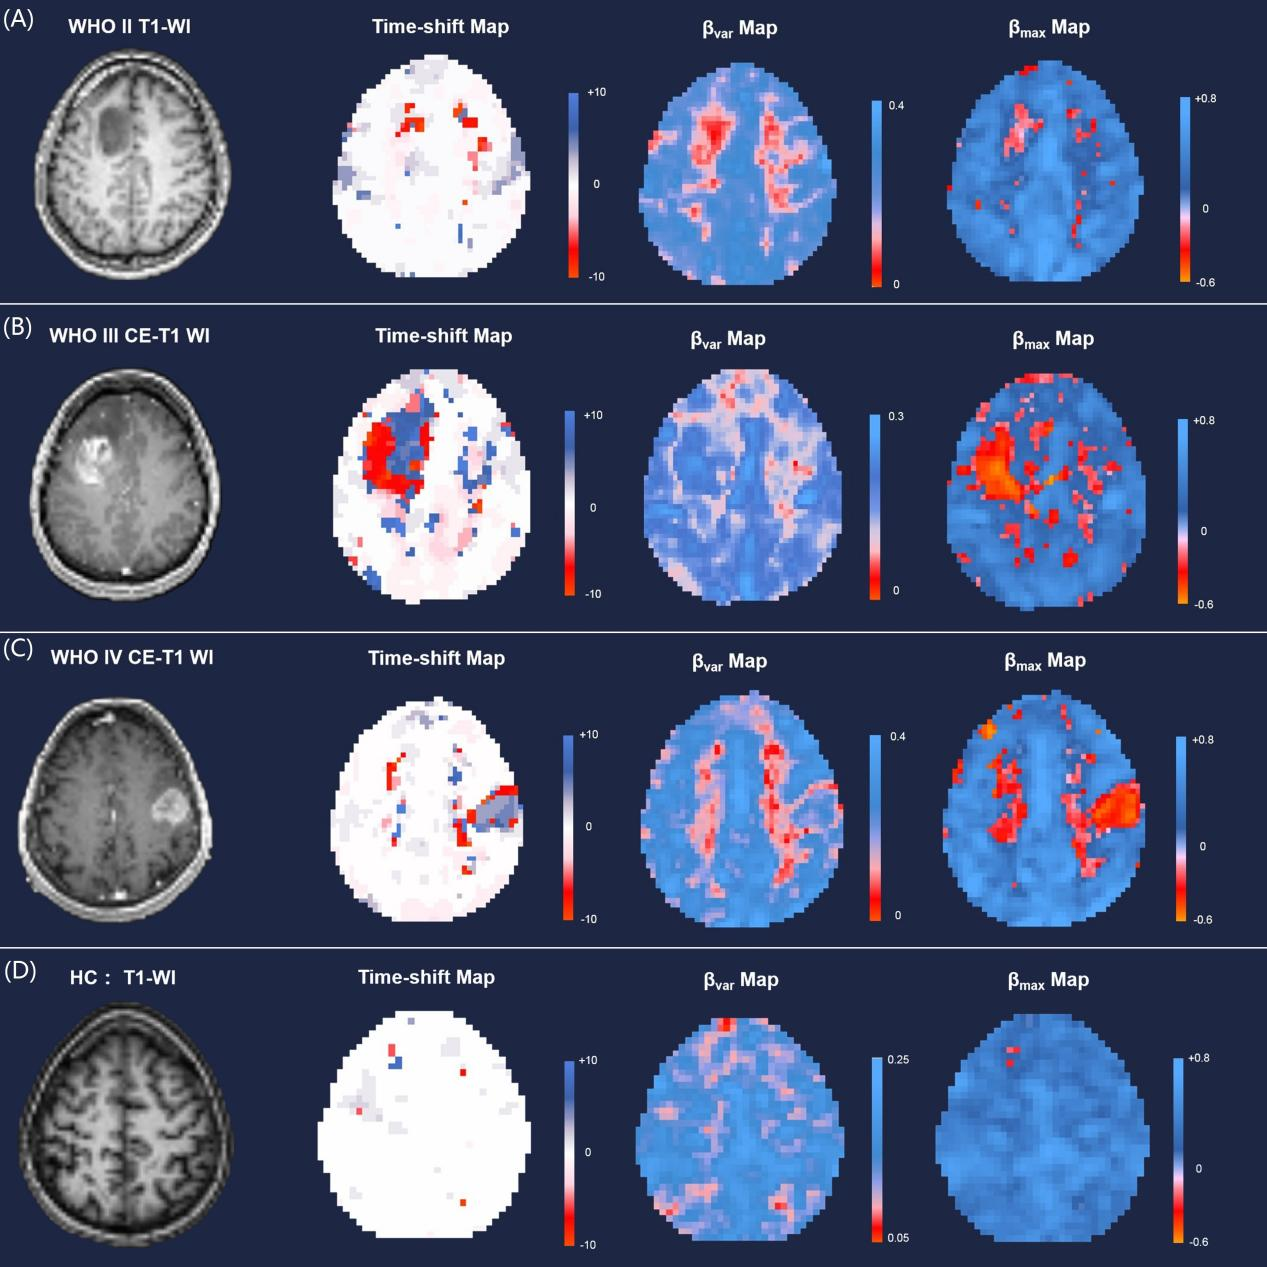

胶质瘤患者和健康对照者BOLD-fMRI时间偏移分析示例。A.WHO II胶质瘤患者(35岁,男性,左额星形细胞瘤); B. WHO III胶质瘤患者(26岁,女性,左额间变型星形细胞瘤); C. WHO IV胶质瘤患者(68岁,女性,右额胶质母细胞瘤); D. 健康被试(HC, 26岁,女性)。

研究团队基于BOLD fMRI数据,顺利获得对系统性低频振荡成分的时间偏移分析(time shift analysis,TSA),在不引入外源性药物对比剂的情况下对全脑血管的功能进行了定量评估。研究发现,胶质瘤及周边水肿区域的血管功能失调主要表现为同步性显著降低,且高度恶性胶质瘤的肿瘤血管开展了具有自主拮抗趋势的动力学模式。肿瘤对侧大脑半球的血管同步性显著增强,并与胶质瘤的生物侵袭性密切相关。基于肿瘤和血管失调的特征,联合决策树模型,该研究工作实现了个体水平的胶质瘤恶性度的准确预测(WHO II/III/IV级同时分类,准确率达90.91%)。上述结果证实胶质瘤在全脑水平触发了血管网络的功能重塑,为深入理解胶质瘤的疾病机理给予了新的参考依据。